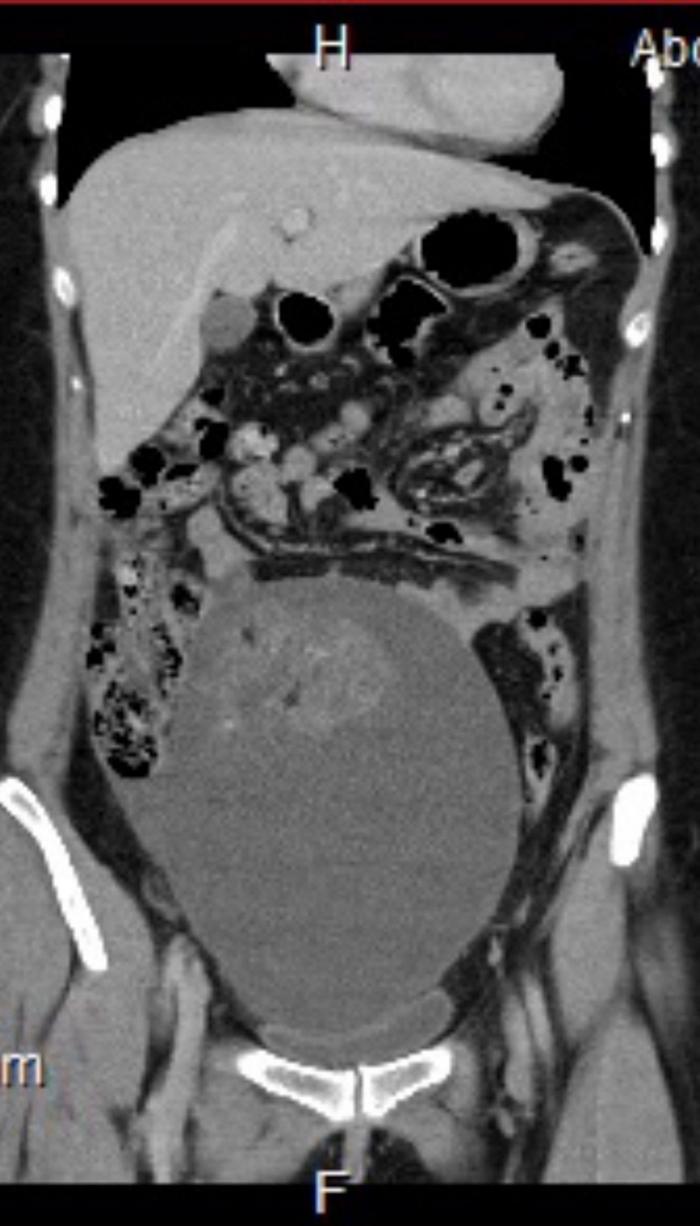

După 7 teste de sarcină, presupusul bebeluș s-a dovedit a fi o tumoră de mărimea unei mingi de fotbal

După dureri groaznice și sângerări între menstruații, o femeie și-a făcut un test de sarcină. Când a venit negativ, a realizat că pericolul era real - altceva se întâmpla cu trupul ei. Medicii, însă, nu i-au putut pune un diagnostic clar, sugerându-i să-și facă alte 7 teste de sarcină. După 3 luni, adevărul a ieșit la iveală